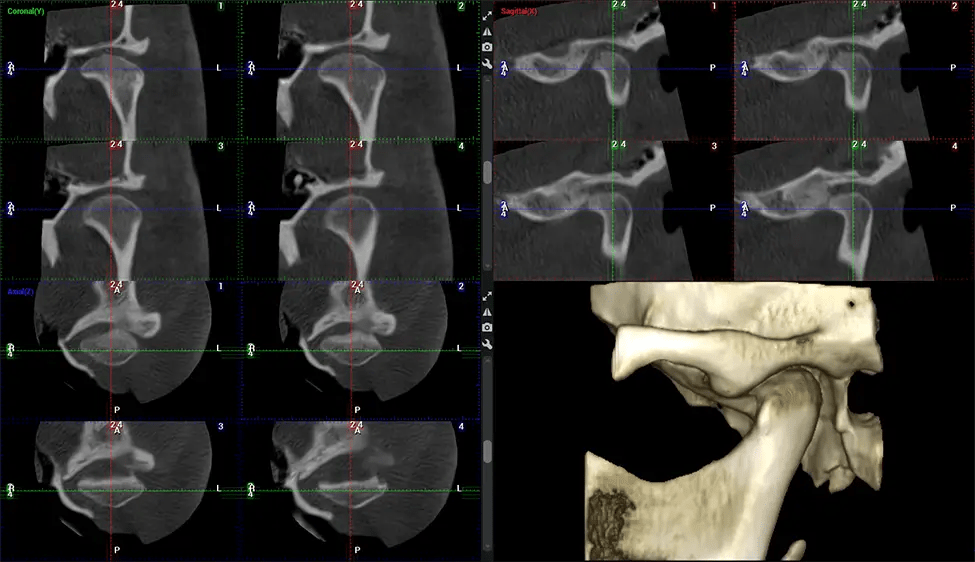

This 3D scan, called cone beam computed tomography, gives your dentist a more complete image of your oral anatomy and disease processes than a traditional X-ray. Unlike conventional X-rays, which capture a 2D image of your mouth from various angles, a 3D scan takes multiple digital X-rays for one image. It provides a complete view of your jaw, teeth, nerves, and soft tissues. This enhanced view allows dentists to detect minor issues not visible in traditional 2D scans, such as impacted wisdom teeth or bone fractures in the sinus cavity.

There are many benefits to using CBCT technology, especially compared to the traditional 2D X-ray format. One of the most significant advantages of CBCT scans is that they provide much more information than traditional X-rays. A scan lets your dentist see images from all angles of your jaw and mouth, including your sinuses, nasal cavity, cheekbones, and other surrounding areas. This added information helps your dentist craft a comprehensive treatment plan that addresses all aspects of your oral health.

Another significant benefit is that 3D imaging provides more precise images of your bone structure. These images are more detailed, providing you with a more accurate diagnosis. An accurate diagnosis means better treatment for you.

After the scanning process, the captured X-ray images are processed by the CBCT software, which applies algorithms to reconstruct a detailed 3D image of the scanned area. The software compiles these individual X-ray images and creates a digital 3D representation of the patient’s anatomy. The reconstructed 3D CBCT image can be viewed and analyzed by the dentist or radiologist. This image can be manipulated, rotated, and zoomed in or out to examine specific structures and evaluate the patient’s condition.

Planmeca Viso G7 CBCT ( Cone Beam CT Scan ) is designed to surpass the demands of industry leaders, specialists, and large institutions. It’s has a large ø25×30 cm sensor with four built-in cameras. It can capture unlimited volume sizes from a ø3×3 cm to a ø30x30cm volume capturing the skullcap through C7 on the cervical spine. The Planmeca Viso G7 offers the industry’s largest single volume scan of ø30×19 cm. It’s poised to handle advanced imaging modalities such as Planmeca ProFace® and Planmeca 4D™ Jaw Motion technology. The occipital head support allows an unimpeded view of facial tissue.